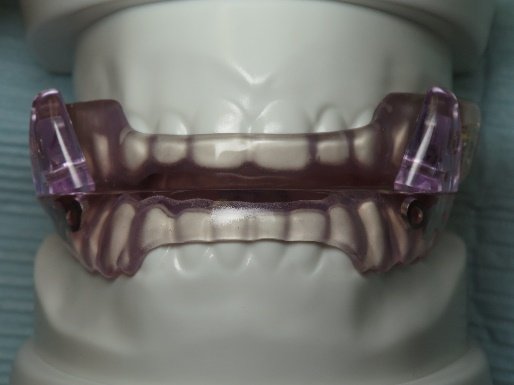

With digital workflows, the fabrication of custom mandibular advancement devices (MADs) has become more efficient. Intraoral scanners capture precise digital impressions, which are then processed by CAD/CAM software to create highly customized devices tailored to individual patients.

🔹 Benefits of Digital Customization:

- More precise fit, improving comfort and compliance.

- Faster production, reducing wait times for patients.

- Adjustability based on AI-predicted treatment response, ensuring effectiveness.

1. Advantages of Digital Workflows in MAD Fabrication

- Precision Fit: Digital intraoral scanning eliminates manual impression errors, ensuring a perfectly tailored appliance.

- Reduced Production Time: 3D printing accelerates the manufacturing process, enabling faster delivery of custom MADs.

- Enhanced Comfort & Compliance: Digitally optimized designs reduce bulkiness, improving patient adaptation and wearability.

2. Material Advancements in 3D-Printed MADs

- Biocompatible resin-based materials enhance durability and flexibility.

- Multi-layer printing allows for personalized stiffness and flexibility zones, optimizing patient comfort.